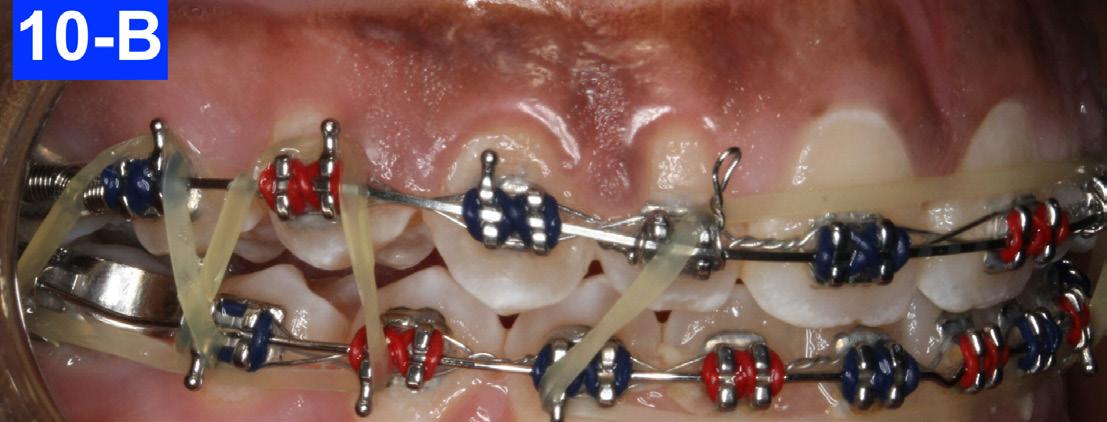

After eleven months of treatment, the overbite had significantly improved. We then placed a .019x025 V- Force 3 (3 force NiTi arch wire – 150/200/300 grams of force) in the maxilla and a .018 SS in the mandible. At this point, a box elastic (5/16 x 6.5 oz) in the anterior sextants was continued along with two triangular elastics (1/4”x 4.5 oz) in the posterior sextants. The posterior triangular elastics were used to close the posterior open bite created by the previous anterior (3) step downs in the maxilla (Figures 10-A, B, C).

Fig. 10-A: V-Force3, frontal view

Fig. 10-B: V-Force3, right lateral view

Fig. 10-C: V-Force3, left lateral view